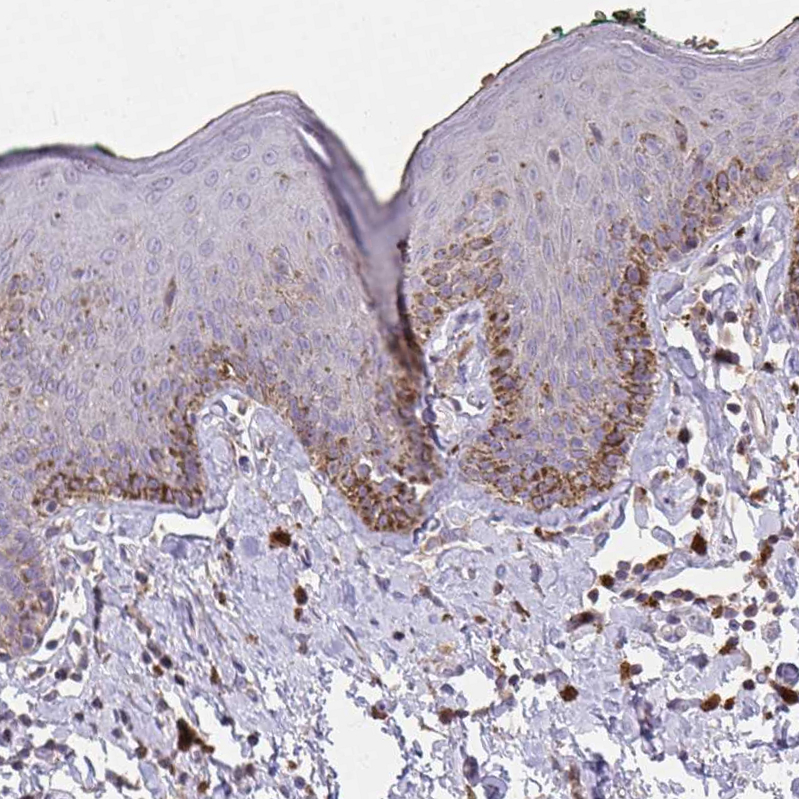

Immunohistochemical staining of human skin shows strong membranous positivity in melanocytes.